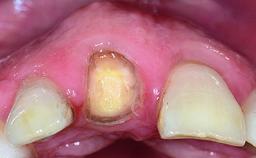

Replacement of a Failing Restored Upper Right Central Incisor, Ridge Preservation and Early Placement of an RC Bone Level Implant

A 23-year-old female, healthy and non-smoking patient had had tooth 11 temporarily restored following a trauma in adolescence. As the patient’s growth had since come to an end and the crown had fractured, she requested an implant-supported restoration of tooth 11. Moreover, the contralateral tooth 21 presented an old composite restoration at the mesial incisal edge. The periodontal tissues were healthy with periodontal probing depth values below 3 mm, but some inflammation was observed around the semi-submerged root of tooth 11.

Soft Tissue Contour and Volume Significantly deficient